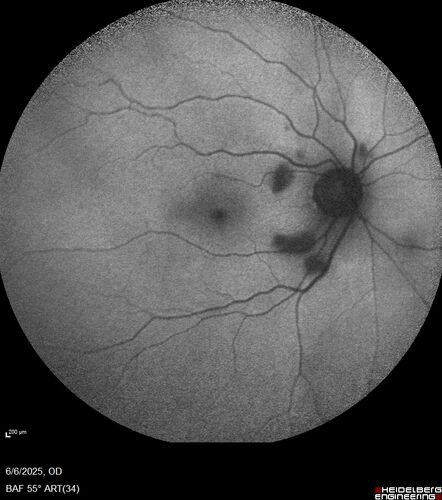

Cotton Wool Spots following cardio-pulmonary bypass

The patient had emergency thoracotomy about 3 weeks ago he had an aortic dissection with a root aneurysm. It had dissected down to the iliacs. The patient had a thoracotomy and aortic valve replacement and large aortic graft.